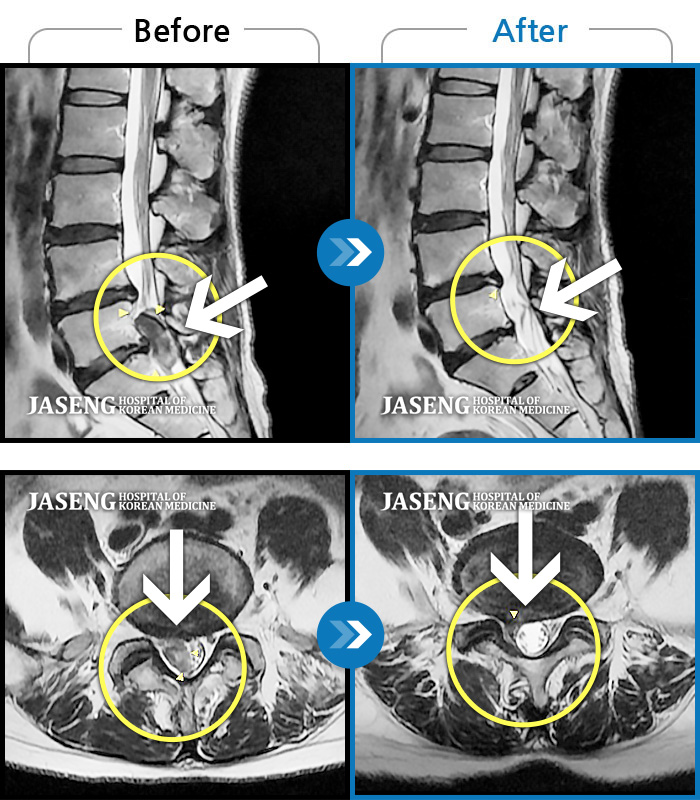

허리디스크

해운대 · 이상건 원장

허리디스크로 인한 요통

촬영시기

2018.04.21 ~ 2018.11.10